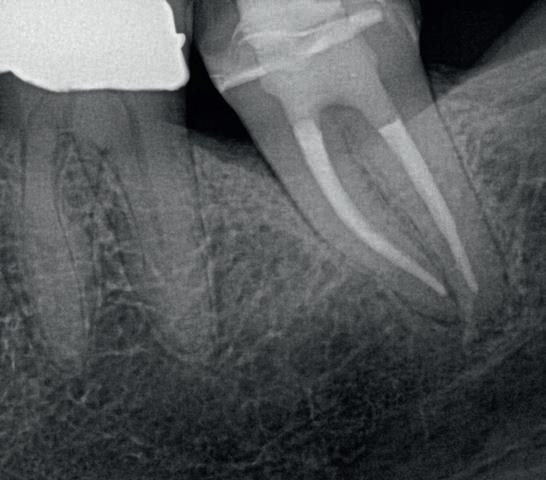

Abb. 4a: Zahn 37: Die präoperative Röntgenaufnahme zeigt eine keramisch adhäsive Versorgung nach Caries profunda, zwei Jahre später: irreversible Pulpitis mit apikaler Parodontitis. –Abb. 4b: Röntgenaufnahme nach der Füllung von Zahn 37: Die endodontische Aufbereitung mit HyFlex EDM OGSF sorgt für schonende Reinigung bei komplexer Kanalanatomie.

Das OGSF-Konzept – also Opener, Glider, Shaper, Finisher – ist logisch aufgebaut, die Feilen sind perfekt aufeinander abgestimmt und „gleiten“ leicht durch den Kanal (Abb. 3). Klinische Bilder und Follow-up-Ergebnisse sehen Sie in einem meiner letzten Patientenfälle, bei dem genau dieses System eingesetzt wurde (Abb. 4a+b).